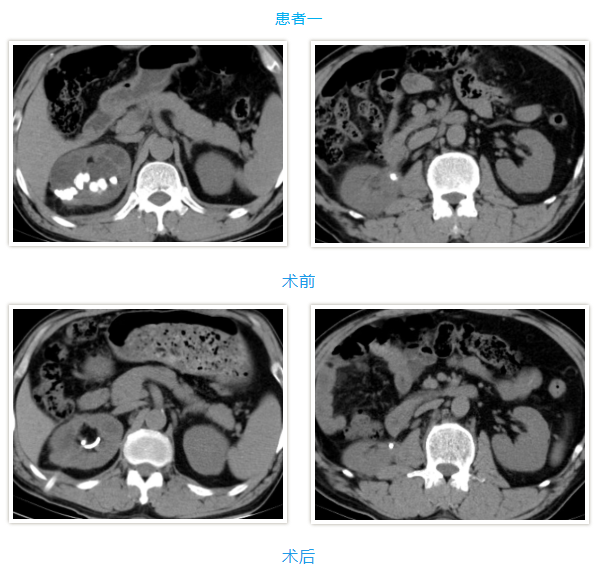

两名患者均为中年男性,入院检查发现肾内多发铸型结石,结石体积大、分布广,其中一例既往患肾行开放取石及经皮肾取石手术,盏颈狭窄伴有肾积水;另一例无明显积水,净石难度高。传统开放手术创伤大、恢复慢,单一微创技术难以彻底清除结石。针对患者病情,泌尿外科团队高度重视,多次组织病例讨论,结合患者身体状况与手术耐受度,最终制定“经皮肾镜+输尿管软镜”联合微创治疗方案。

在泌尿外科团队及麻醉科团队成员密切配合。患者取斜仰截石位,先通过输尿管软镜探查输尿管及肾盂肾盏情况,精准定位结石;随后在超声引导下建立经皮肾通道,置入经皮肾镜,利用钬激光碎石设备将复杂结石击碎成细小颗粒,部分结石因角度问题经皮肾镜无法够到,则通过软镜配合取石篮将结石拖入经皮肾通道口进行彻底清除。整个手术过程创伤小、出血少,术后患者恢复顺利,未出现相关并发症,现已康复出院。